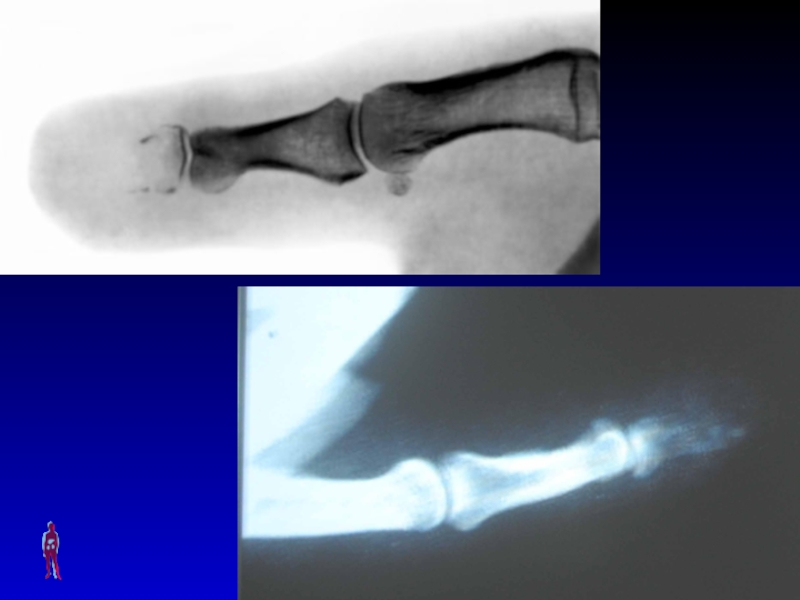

Слайд 60Суставной панариций.

Возникает после ранения межфаланговых или фаланговых областей пальца с

их дорсальной поверхности, где суставы прикрыты лишь тонким слоем мягких

тканей. Воспаленный сустав приобретает веретенообразную форму, тыльные межфаланговые борозды сглаживаются. Попытка к сгибательно-разгибательным движениям пальца приводит к резкому усилению болей в пораженном суставе. При вовлечении в воспалительный процесс связочного, хрящевого и костного аппарата пальца, возникает патологическая подвижность и ощущение крепитации шероховатых частей суставных поверхностей. Такая «разболтанность» сустава свидетельствует о значительном изменении костно-хрящевого аппарата пальца.

Суставной панариций.Возникает после ранения межфаланговых или фаланговых областей пальца с их дорсальной поверхности, где суставы прикрыты лишь

Слайд 61СУСТАВНОЙ ПАНАРИЦИЙ

Симптомы: местные (боль при движениях, ограничение движений в суставе,

веретенообразная форма пальца из-за отека сустава, гиперемия) и общие (симптомы

интоксикации).

Лечение: хирургическое (при серозном воспалении возможно проведение пункции с удалением экссудата и введением в полость сустава А/Б, при гнойном процессе – артротомия с последующим дренированием и промыванием полости сустава) + консервативная комплексная терапия.

Слайд 63КОСТНЫЙ ПАНАРИЦИЙ

Симптомы: местные (болезненный отек всей фаланги, гиперемия, локальная гипертермия)

и общие (выраженные симптомы интоксикации).

Лечение: хирургическое (некрэктомия участков фаланги или

удаление всей фаланги) + консервативная комплексная терапия.